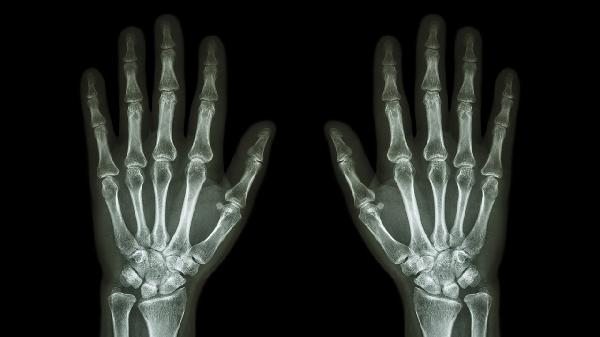

4、骨关节炎:

关节软骨退行性变多见于中老年人,晨起时关节疼痛僵硬但持续时间较短。X线检查可见关节间隙变窄。治疗包括关节腔注射透明质酸和口服氨基葡萄糖。